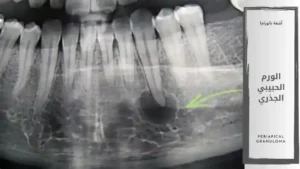

الورم الحبيبي الذروي | آفة التهابية مزمنة حول الجذر الورم الحبيبي الجذري Periapical Granuloma ويُعرف أيضًا باسم الورم الحبيبي الذروي وهو آفة التهابية مزمنة غير